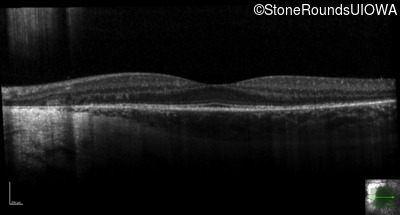

Optical Coherence Tomography - Right - 20/16

Exemplar / OCT Stack